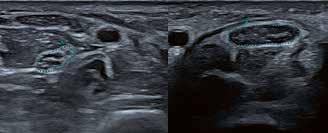

Hochauflösender Ultraschall in der Sportpraxis

Dr. Axel Schramm.

Veranstaltungen & Workshops 2021/22

2021

21.08. Berlin

BNK Niederlassungsseminar

28.08. Hannover

Niedersächsischer Gynäkologentag

02. – 04.09. Münster

61. DGH-Kongress

03. – 04.09. Leipzig

3. Anwenderseminar Muskel- und Nervensonographie

15. – 18.09. Stuttgart

73. Kongress der Deutschen Gesellschaft für Urologie

13. – 18.09. Leipzig

Viszeralmedizin 2021

17. – 18.09. Würzburg

CEUS in Dresden IX

30.09. – 02.10. Landshut/Essenbach

73. Jahrestagung und MTRA-Tagung der Bayerischen Röntgengesellschaft 2021

03.10. Hofheim, Digital

22. Hofheimer Tierärztetag und 8. Tagung für Tiermedizinische Fachangestellte

06. – 08.10. Digital

56. Jahrestagung der Deutschen Gesellschaft

für Neuroradiologie e.V. (neuroRAD 2021)

06. – 09.10. Berlin, Hybrid

Kongress für Kinder- und Jugendmedizin 2021 (DGKJ)

22. – 23.10. Hamburg

Uro-Andrologisches Symposium –Meet the Experts

27. – 29.10. Wien

Ultraschall 2021 (DLT)

03.11. Stuttgart

Canon SONOSALES

04. – 05.11. Dortmund

13. RadiologieKongressRuhr

04. – 06.11. Rostock-Warnemünde

Ultraschall in Warnemünde 2021

06.11. München

10.11. Frankfurt

12.11. Neuss

13.11. Chemnitz

9. Mitteldeutsche Tagung Neonatologie und Pädiatrische Intensivmedizin (MITANPI)

18. – 20.11. Berlin

DVG-Vet-Congress 2021

20.11. Rheine

12. Rheiner Symposium für Gynäkologie und Perinatalmedizin

20.11. Essen

27.11. Hamburg

04.12. Dresden

09. – 11.12. Berlin, Hybrid EuroEcho 2021

2022

14. – 15.01. Köln

Update RSNA

22.01. Dortmund

DEGUM Refresher-Kurs Dopplersonographie

11. – 12.02. Hamburg

04. – 05.02.

Radiologiekongress Nord

Baden-Baden

Frühjahrskurse der VSRN

27. – 26.06. Wiesbaden, Hybrid

103. Deutscher Röntgenkongress

Immer aktuell – online unter: https://de.medical.canon/events/

Präsenz Hybrid Digital

Termine // CT, MR, Röntgen und Ultraschall // 2021/22

DATUM ORT/VERANSTALTUNG DATUM ORT/VERANSTALTUNG

VISIONS 31 // 63 © 2021 C ANON MEDICAL SYSTEM S

Gelenkerkrankungen im Kindesalter